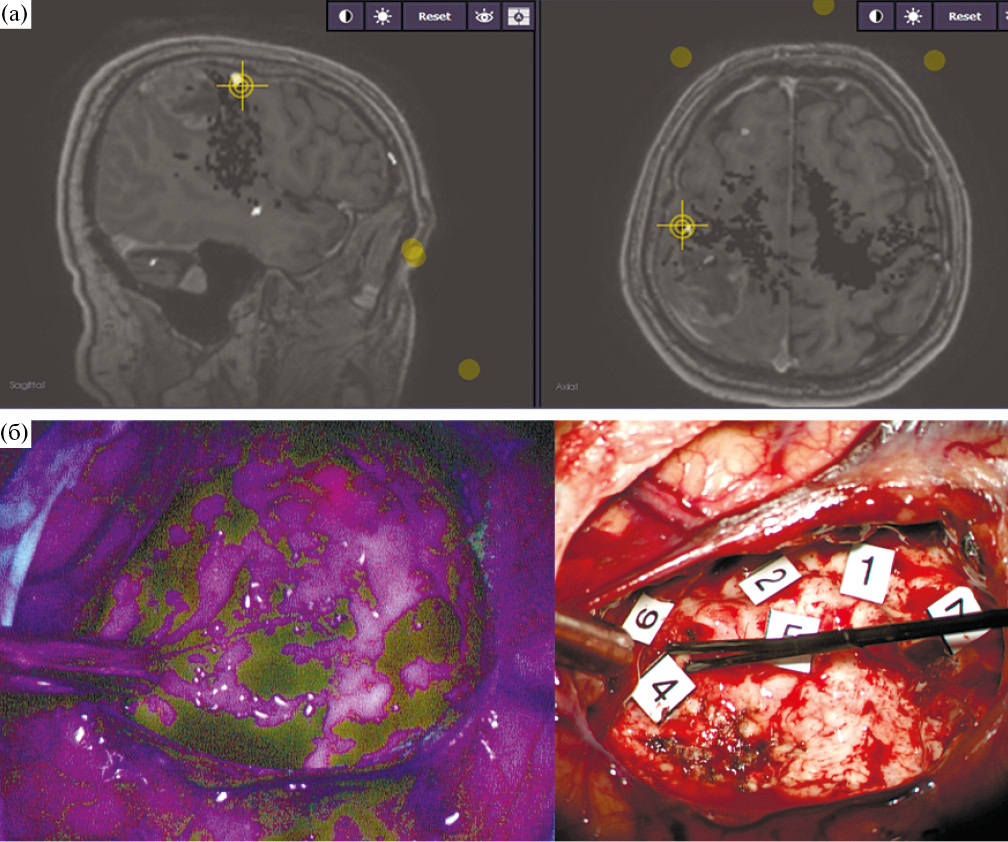

Интраоперационная оценка радикальности удаления также значимо не отличалась в контрольной и основной группах (р = 0.812). В контрольной группе хирург предполагал наличие остатков опухолевой ткани в 45.5% случаев, в основной – в 39.2%. При этом у 12 пациентов основной группы (19%), по данным протоколов операции, данные ФМ были использованы как основание для расширения резекции. Основными причинами остановки резекции были распространенный характер опухоли с инфильтрацией глубинных структур головного мозга, переходом на противоположное полушарие и фиксация к магистральным кровеносным сосудам (12 пациентов: 7 – в основной группе и 6 – в контрольной) и, что более принципиально в данной выборке, появление моторных ответов при ПКС и ПСС (16 пациентов: 15 – в основной группе и 1 – в контрольной) и снижение ТК МВП (2 пациента из основной группы и 1 – из контрольной). Таким образом, в основной группе в большем количестве случаев резекция была ограничена ввиду объективных лимитирующих причин. Интересным фактом является то, что у трех пациентов из основной группы положительные моторные ответы были получены при стимуляции в участках с интенсивной флуоресценцией при пороговой силе тока в 5 мА, что в очередной раз подтверждает инфильтративный характер роста глиальных опухолей и возможность включения в строму опухоли нормально функционирующей мозговой ткани (рис. 2).

Рис. 2. (а) – интраоперационная фотография ложа удаленной опухоли у пациента с глиобластомой левой лобной доли в «белом свете». Визуально определяется неизмененное мозговое вещество, при прямой субкортикальной биполярной и монополярной стимуляции с пороговой силой тока 5 мА в этой области получены моторные ответы с языка. (б) – интраоперационноая фотография той же области. В зоне стимуляции определяется яркая розовая флуоресценция, что свидетельствует о наличии опухолевой ткани. У данного пациента резекция была остановлена.

Fig. 2. There are motor responses by direct bipolar with a threshold current of 5 mA stimulation in the bright pink fluorescence area.